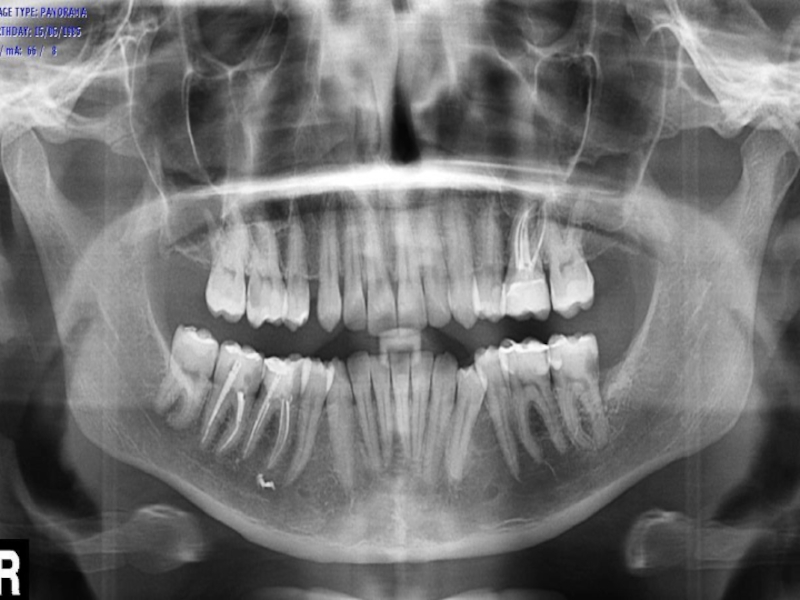

Слайд 6Сильное нарушение зубного ряда и смещение зубов;

Нестандартное положение зубов;

Заболевания десен,

в особенности пародонтит;

Кровоточивость десен;

Быстрое скопление зубных отложений вокруг корня зуба;

Ярко

выраженные десневые карманы;

Обнаженные корни зубов;

Показания к шинированию:

Сильное нарушение зубного ряда и смещение зубов;Нестандартное положение зубов;Заболевания десен, в особенности пародонтит;Кровоточивость десен;Быстрое скопление зубных отложений